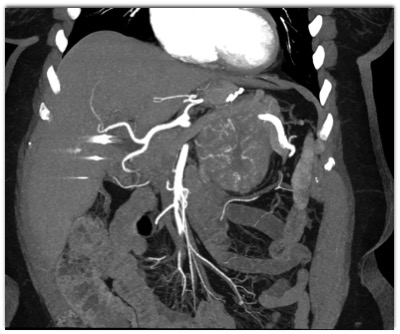

The most likely diagnosis in this case is?

adrenal carcinoma

adrenal lymphoma

pheochromocytoma

adrenal hemorrhage